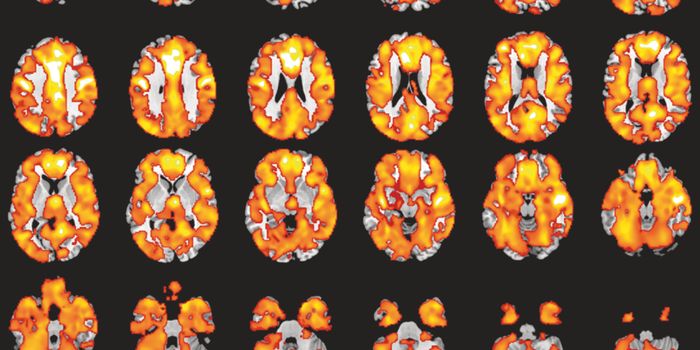

JUN 09, 2024NeuroscienceResearchers developed a method to predict dementia with over 80% accuracy up to nine years before diagnosis using fMrI s ...